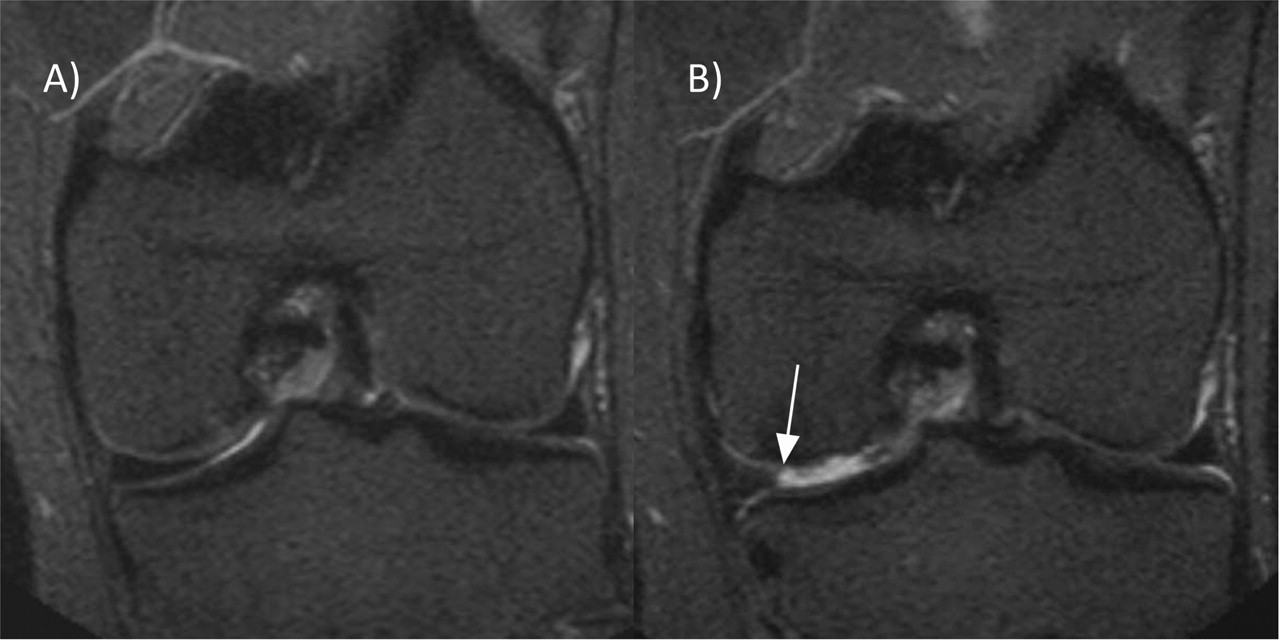

A medial meniscus posterior horn (MMPH) horizontal tear with a combined... Download Scientific

A medial meniscus posterior horn (MMPH) horizontal tear with a combined... Download Scientific Macerated Posterior Horn Medial Meniscus Classification of meniscus extrusion and tear, meniscotibial ligament (mtl), and medial meniscus posterior root grading system. Posterior horn tears are common and located in the back of the meniscus. The posterior horn of the medial meniscus is the posterior third of the medial meniscus. Central tears are on the inner side of the meniscus. It is the thickest portion and. Macerated Posterior Horn Medial Meniscus.